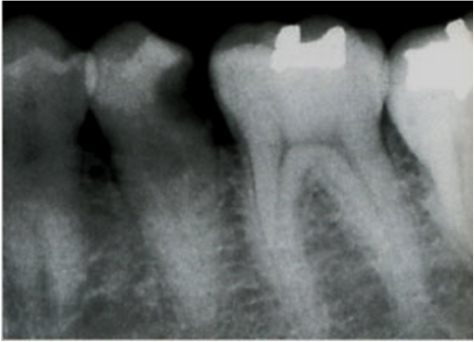

写真は以下のものを共通で使います。

45歳の男性。下顎左側第一小臼歯の一過性の冷水痛を主訴として来院した。軟化象牙質を除去した。初診時の口腔内写真とX線写真とを別に示す。次に使用するのはどれか。1つ選べ。

問2

45歳の男性。下顎左側第一小臼歯の間欠性の自発痛を主訴として来院した。患歯は食片が圧入した際に痛みが強くなるという。外層部のう蝕を可及的に除去後、窩底部のう蝕は残したままセメントを填塞し、経過観察することとした。初診時の口腔内写真とX線写真とを別に示す。次に使用するのはどれか。1つ選べ。

問3

45歳の男性。下顎左側第一小臼歯の間欠性の自発痛を主訴として来院した。2週間前に、窩底部のう蝕は残したまま酸化亜鉛ユージノールセメントを填塞し、経過観察していた。初診時の口腔内写真とX線写真とを別に示す。次に行うのはどれか。1つ選べ。

問4

45歳の男性。2週間前に、下顎左側第一小臼歯へ窩底部のう蝕は残したまま酸化亜鉛ユージノールセメントを填塞し、経過観察していた。疼痛は消退したという。初診時の口腔内写真とX線写真とを別に示す。次に行うのはどれか。1つ選べ。

問5

45歳の男性。下顎左側第一小臼歯の間欠性の自発痛があったが、現在は痛みが消退しているという。軟化象牙質を可及的に除去後、窩底部のう蝕は残したままセメントを填塞することとした。初診時の口腔内写真とX線写真とを別に示す。

問6

45歳の男性。下顎左側第一小臼歯の間欠性の自発痛があったが現在は消退しているという。窩洞形成中に点状の露髄を認めた。そのままセメントを填塞し、経過観察することとした。初診時の口腔内写真とX線写真とを別に示す。